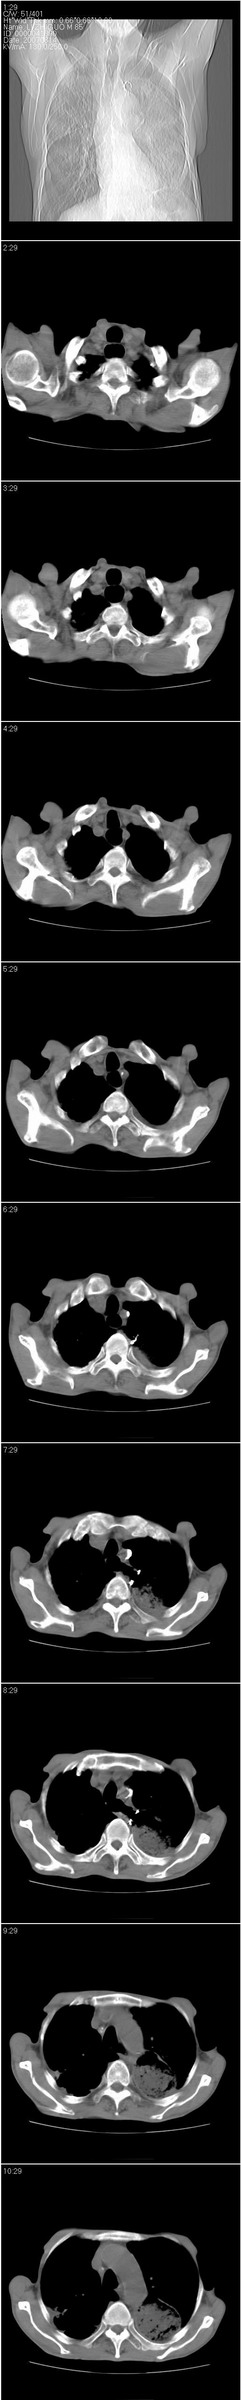

以下是引用dyqct在2007-8-18 14:40:00的发言:[br]考虑:1、食道弓上吻合术后(左侧胸腔胃);[br] 2、右上继发型肺结核;[br] 3、慢性支气管炎合并全小叶型肺气肿、感染。

以下是引用andymaomao在2007-8-18 14:29:00的发言:[br][br]1.该患者应有食道ca手术史,胃位于左侧胸腔(后纵膈旁);[br]2.双肺继发性肺tb?!不排除部分病灶改变为转移灶;[br]3.纵隔气管旁可见肿大淋巴结;[br]4.右下侧后胸壁轻度增厚、粘连。[br]5.另左肺部分肺组织含气不良(受压!?)。[br][br]